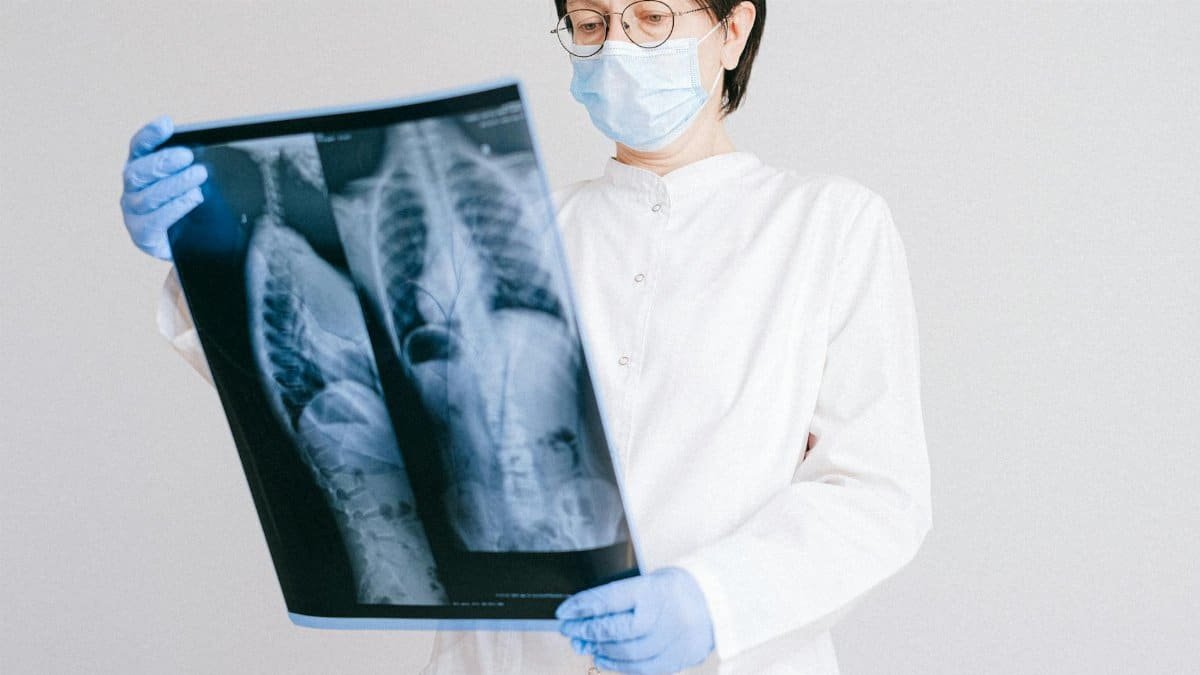

“I’m bionic now.” With those three words, Channing Tatum delivered a stark update on his health, sharing graphic X-rays of his reconstructed shoulder on February 4, 2026. The images reveal screws and plates securing the joint after major surgery. This raw glimpse into Channing Tatum health highlights the actor’s resilience amid physical challenges. Fans watched as the Hollywood star laid bare his recovery process, turning a personal ordeal into public conversation.

Channing Tatum did not mince words. On X, formerly Twitter, he posted X-rays exposing the metal hardware inside his shoulder. “I’m bionic now,” he wrote, embracing the term with gritty humor. This declaration marks a pivotal moment in Channing Tatum health narrative. The post, dated February 4, 2026, pulled back the curtain on a surgery that demanded extensive reconstruction. Tatum’s directness underscores his no-nonsense approach to recovery, signaling strength despite vulnerability.

Graphic X-Rays Go Public

The X-rays Tatum shared were unflinching. Clear images displayed a shoulder pieced together with precision engineering. Screws dotted the bone structure, while plates bridged fragile areas. These visuals offered an unfiltered look at post-surgical reality. In the world of celebrity updates, such transparency stands out. Tatum’s choice to post them himself amplified the impact, making Channing Tatum health a trending topic overnight. The photos served as proof of the procedure’s intensity.

Major Reconstructive Surgery Details

Major reconstructive surgery transformed Tatum’s shoulder. The operation addressed severe damage, requiring hardware to stabilize the joint. Plates and screws now hold everything in place, a common fix for complex injuries. For context, such procedures often follow trauma or degeneration, though Tatum kept specifics close. This intervention reflects advanced orthopedic techniques available in 2026. Tatum’s case exemplifies how stars confront physical limits head-on. Recovery from such work demands time and discipline.

Screws and Plates: The Hardware Breakdown

Zooming into the X-rays, screws anchor deep into bone, preventing shifts during healing. Plates overlay fractures or weakened sections, distributing stress evenly. Tatum’s images showcased this setup vividly—metal gleaming against shadowed tissue. This “bionic” reinforcement is key to restoring function. In Channing Tatum health terms, it means a shoulder rebuilt for action. Such implants, made from biocompatible titanium, integrate over months. Tatum’s reveal demystifies the process for everyday audiences.